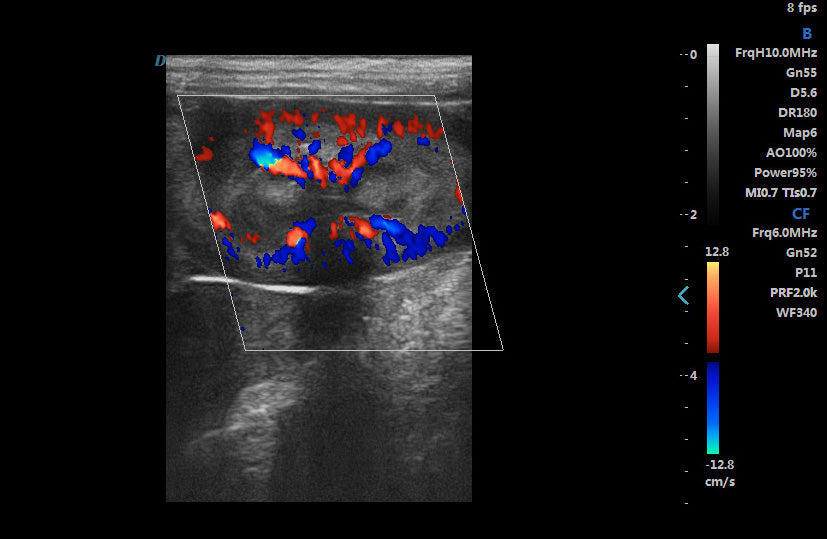

2. Excellent image processing functions, including spectral pulse Doppler, directional energy Doppler, spatial composite imaging, and tissue harmonic imaging technology.

Spectral Pulse Doppler

Directional Energy Doppler

Real-time Triplex

6. The application range is very wide, including universities, research institutions on the rat heart and cranial, vascular blood flow, tumor detection, thrombus detection; experimental institutions on the rabbit blood vessel detection, real-time detection of blood flow, heart function, rabbit tumor detection; widely used in pet hospitals, pet clinics, pet stores, zoos, abdominal organs, superficial organs, heart, blood flow effects, etc.; fish The technology of checking fish roe/white/bubble/gonad, etc., for sturgeon egg size, fullness and egg quality control.